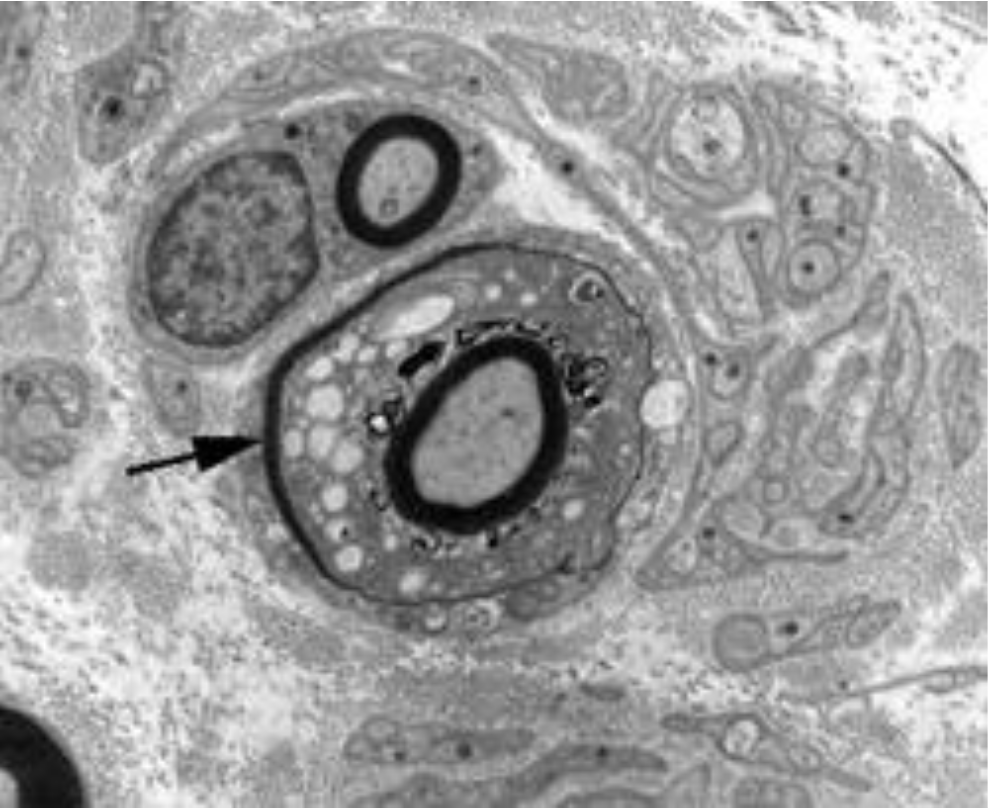

What can be seen in the image below?

Normal myelinated nerve fiber:Which axonal and Schwann cell organelles can you see?.

Note collagen fibers in the endoneurium

Neural tubules and filaments seen in the middle.

Myeline sheath appears black b/c of fixative used (osteum? preserved myelin sheath).